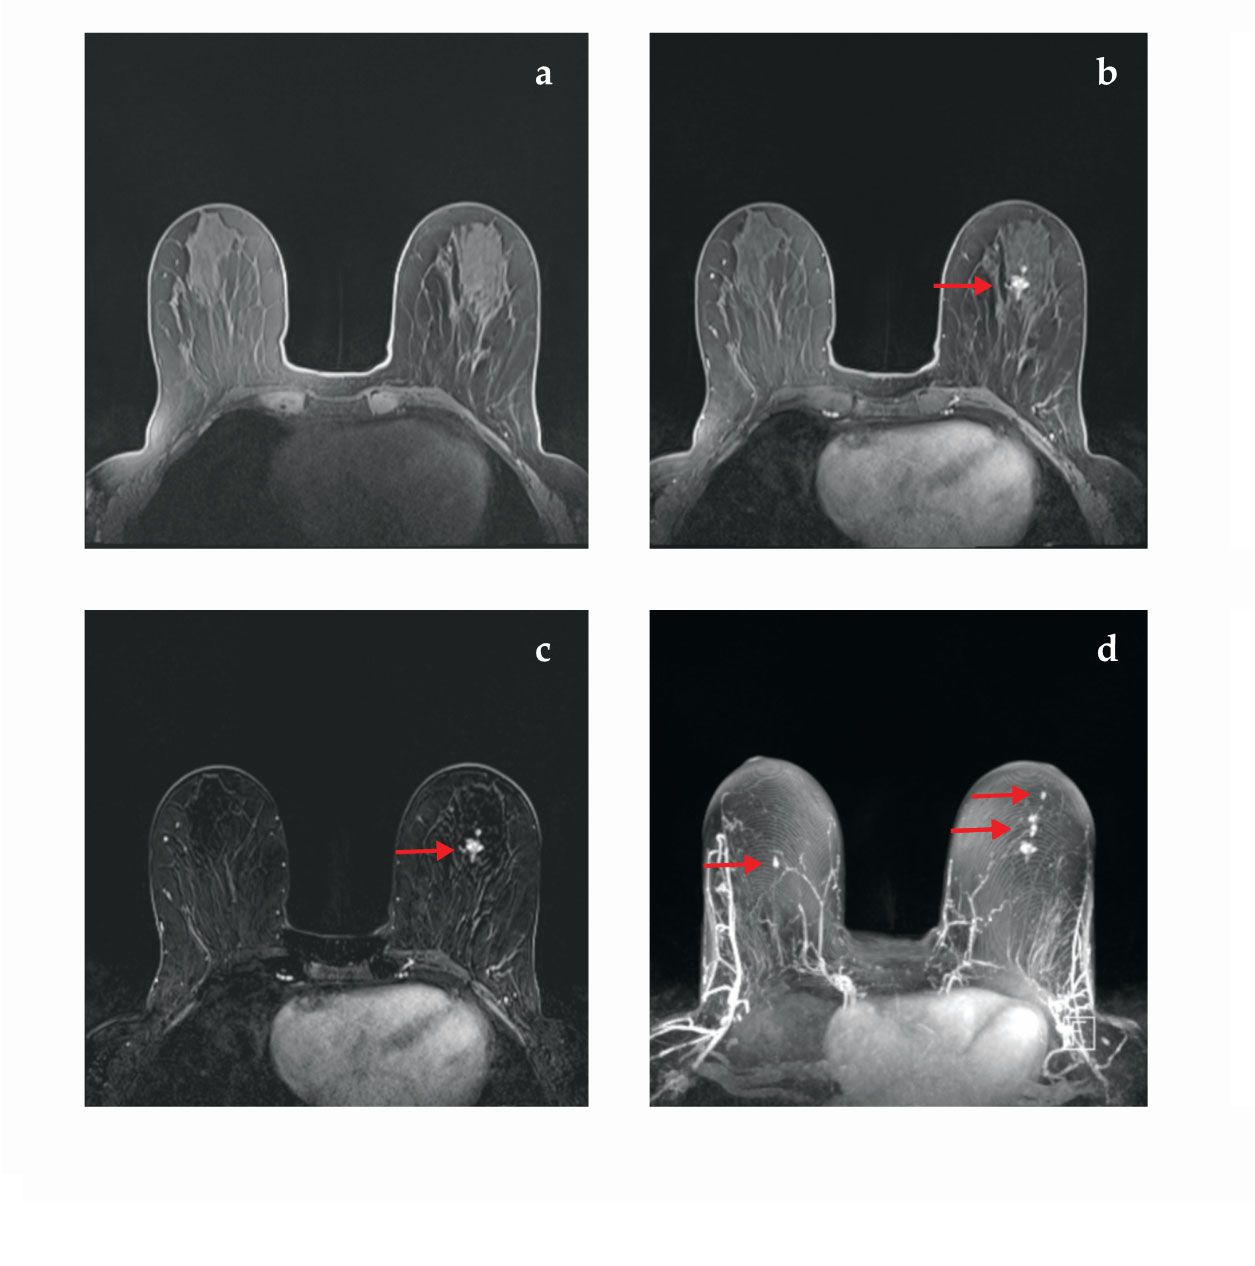

In fast-screening breast MRI, a single scan is performed on both breasts simultaneously; Gd dye is injected and the same scan is then repeated. The first image is subtracted from the second, which ideally removes all the tissue from view except for the locations containing dye in the second scan. Individual slices of imaged tissue are fused together into a volume using the so-called maximum intensity projection technique. The fusion allows the radiologist to view all the dye-flow information in a pseudo-3D slab without having to scroll through images of individual slices (see figure 4 and the image on the title page of this article). She can thus easily detect tumors that recruit new blood flow in a matter of seconds following a three-minute MRI scan. 14

Figure 4.

Fast-screening breast MRI. (a) In this T1-weighted image without contrast dye, no abnormalities are apparent. (b) With contrast dye injected into the tissue, this T1-weighted image shows a large lesion (red arrow) that’s easily seen. (c) This subtracted image, panel b minus panel a, improves the tumor’s visibility and the brightness of dense glandular tissue. (d) A so-called maximum intensity projection of all subtracted slices (such as panel c) reveals other small lesions (red arrows), including one in the contralateral breast. A radiologist can much more rapidly detect all suspicious lesions by viewing a single image of this type than by individually reviewing dozens of image slices. (Images by David Jordan, University Hospitals Cleveland Medical Center.)